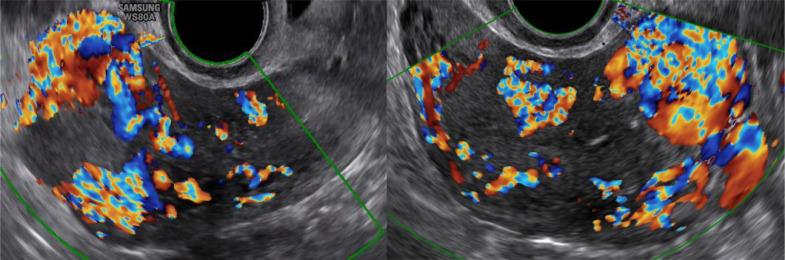

Uterine arteriovenous malformation (AVM) is a rare condition that may lead to a life-threatening state. The urgency of diagnosis and treatment for uterine AVM should be emphasized. This case report describes a 42-year-old woman with a vaginal hemorrhage. In the previous month, the patient also had a hemorrhage after induced abortion that required a bilateral artery suture hemostasis of the uterus. On ultrasound, there was a lesion suspected by acquired AVM. Magnetic Resonance Angiography and Digital Subtraction Angiography was indicated to confirm the diagnosis. The patient was successfully treated by uterine artery embolization. After 6 months, the re-examined result showed no lesion of AVM.

Color Doppler US in the evaluation of uterine vascular abnormalities.彩色多普勒超声在子宫血管异常评估中的应用

Radiographics. 2002 Jan-Feb;22(1):47-53. doi: 10.1148/radiographics.22.1.g02ja0947.